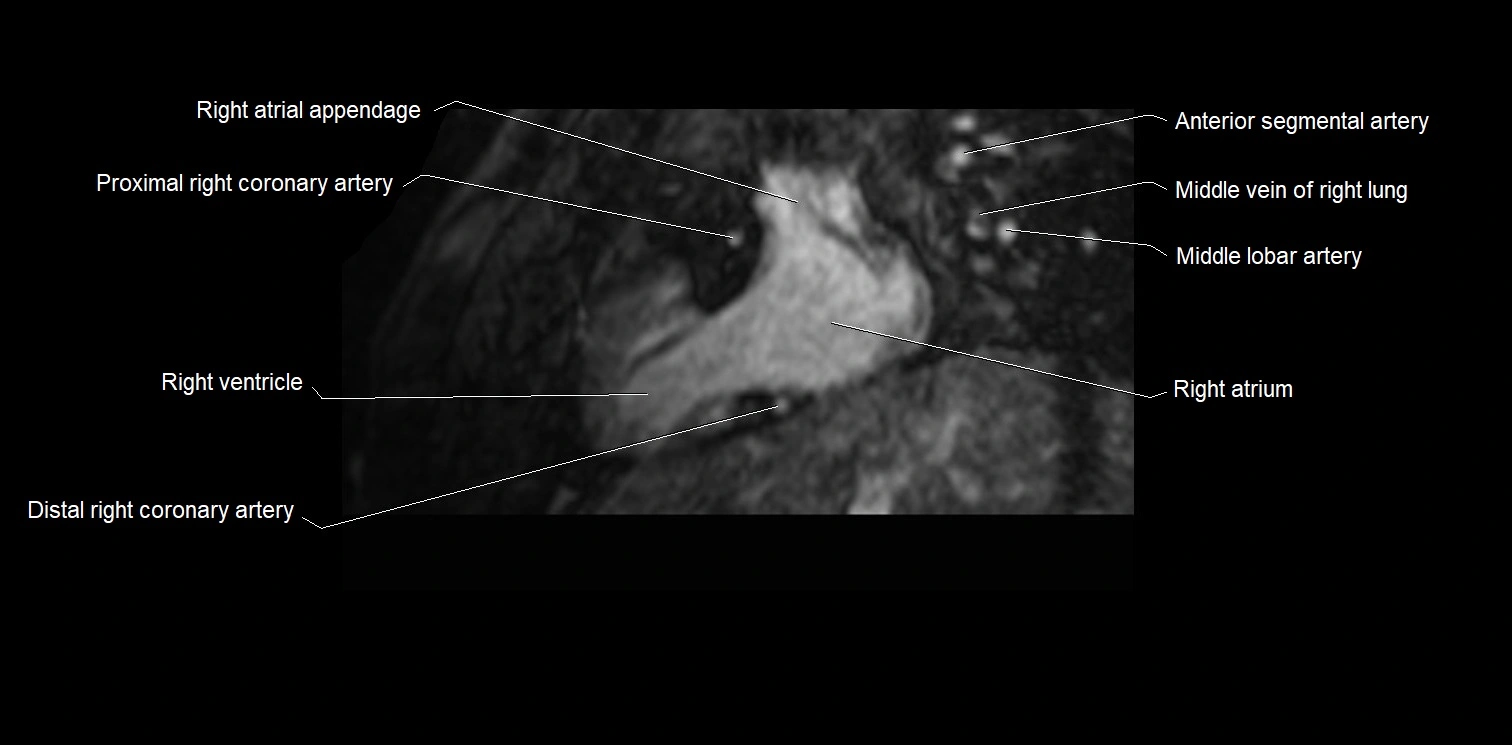

- Right auricle of heart

- Right coronary artery (RCA)

- Right ventricle

- Right atrium

- Middle lobar artery of right lung